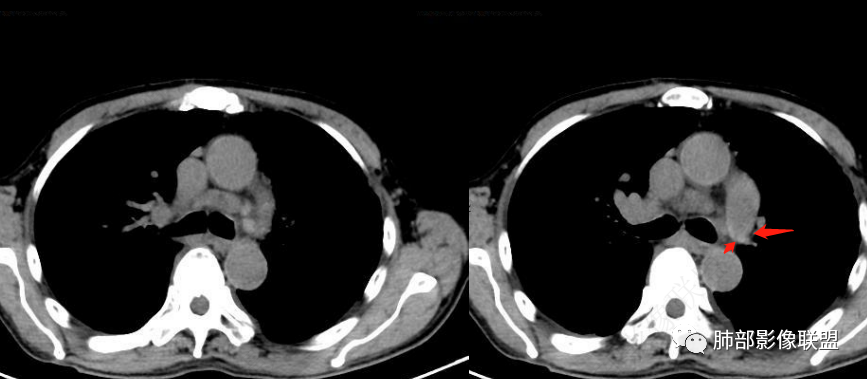

看一下影像,肺动脉粗大,大于升主动脉

从肺动脉的主体分析:左肺动脉好像起始部就开始狭窄。

现在给的图像:是鼠尾状狭窄,而不会局部膨隆,远端细小那种。

右侧的肺动脉增粗肯定与代偿有关。

现在的问题是自左肺动脉狭窄的原因:是急性栓塞?炎性病变?慢性血栓?

4、肺动脉改变:左肺动脉起始部突然狭窄(右肺动脉代偿增大——继发肺内改变)

7.肺动脉主干扩张,左侧肺动脉主干见混杂密度影,上下肺动脉似不能连续追踪。

(增强:左肺动脉充盈缺损、闭塞)